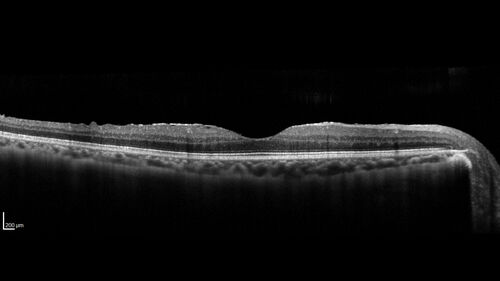

Recurrent Toxoplasmosis Right eye then Left eye 8 years later

33 year old brazilian man. Initially presented with uveitis in the right eye in 2011. Then in the left eye in 2019. Since has had two more episodes.